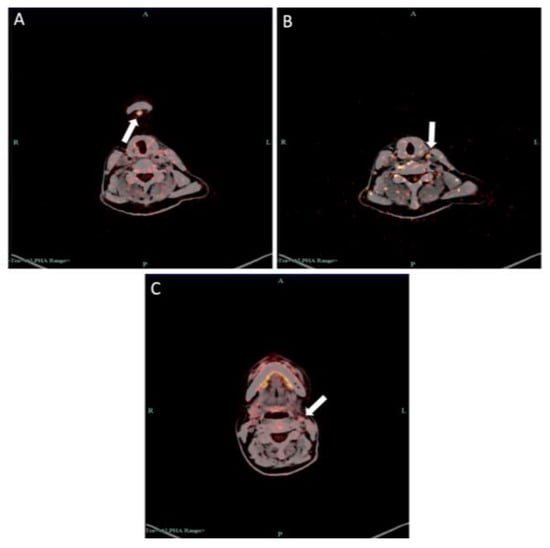

2.1. Case 1